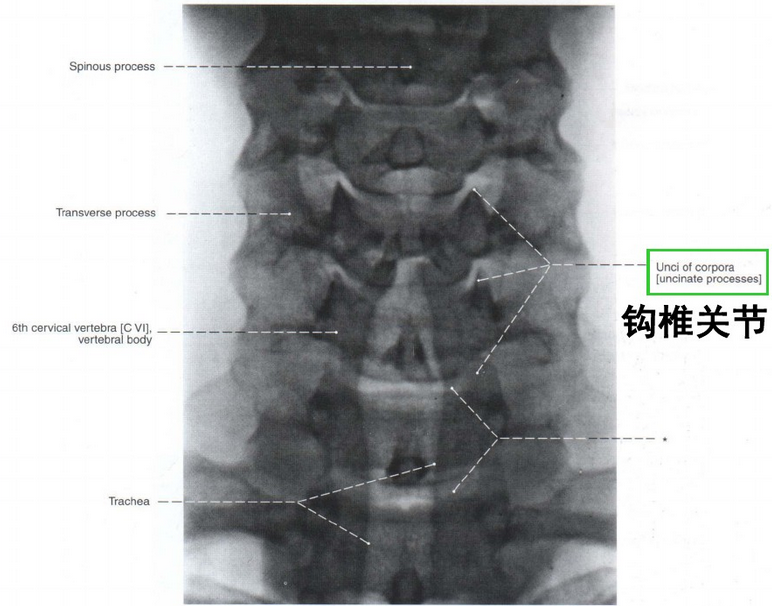

钩椎关节

颈椎钩椎关节x图片